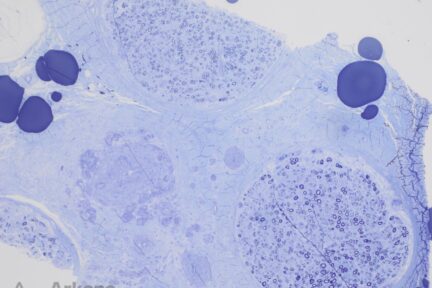

Lipid Storage Myopathy in 77-Year-Old Patient

Clinical History:The patient is a 77-year-old female with several months of progressive muscle weakness predominantly in her upper and lower…